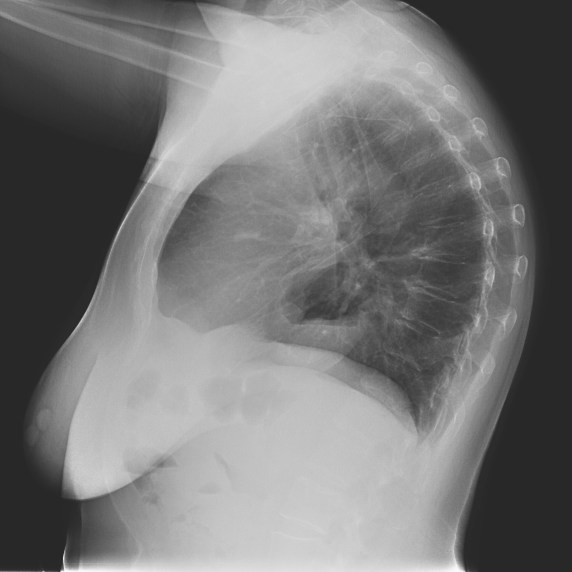

Nota: ¡¡¡No olvidar la placa lateral!!! La regla a seguir es la misma. Leer abdomen y diafragma, examinar parte posterior, tejidos blandos y subir por la columna; tráquea y descender por mediastino. Finalmente pulmones.

Solución: Es un estudio Normal. Silueta cardiomediastínica y parénquimas pulmonares sin alteraciones significativas.